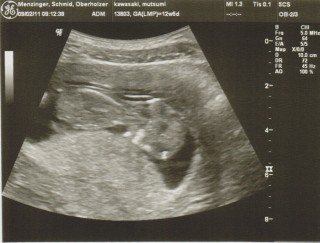

スイスより、12週5日目です。

前回の検診の時は眠っていて全く動いてくれなかったけど、

今回はダンスをしているような激しい動きで先生を手こずらせる程。

「ママにキスをしているね」と先生に言われた写真です。